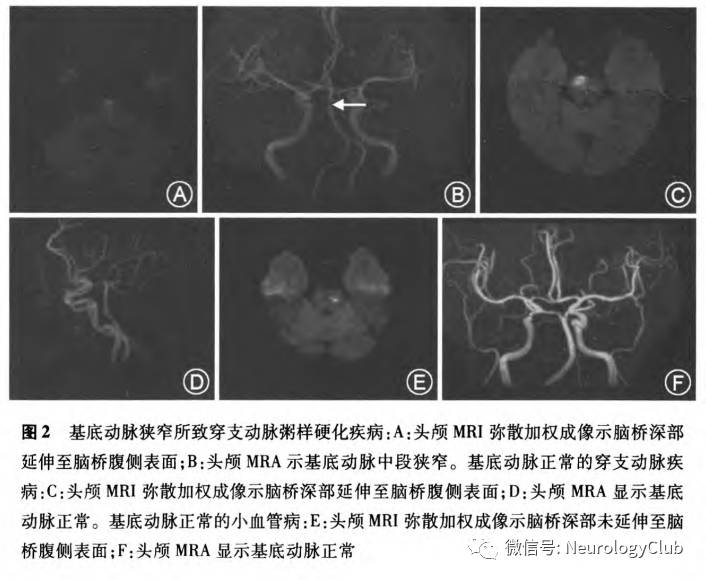

2. 临床诊断:目前临床上主要是通过MRI DWI上梗死灶与载体动脉的位置关系来确定(图1)。不同研究所采用的定义尚不统一。Yamamoto等将BAD定义为DWI上累及基底节区3个或以上层面且直径大于10mm的孤立梗死灶。Nakase等将BAD定义为DWI上累及基底节区3个或以上层面且直径>15mm的孤立梗死灶。Jeong等将BAD定义为在层厚为5mm的头颅MRI检测中,病灶在DWI上累及基底节区4个层面。Nah等将大脑中动脉供血区BAD定义为梗死灶累及基底节的最底部,且梗死灶大小限定为≤20mm。关于基底动脉穿支动脉疾病的定义比较明确(图2):在脑桥旁正中动脉供血区,梗死病灶在头部轴位DWI上由脑桥深部延伸至脑桥腹侧表面

与小血管病相比较,BAD血管病变位于穿支动脉近端。因此缺血性病灶大于经典的LI患者。Cho等研究了豆纹动脉供血区的单个皮质下梗死,结果显示存在大脑中动脉狭窄的患者梗死灶较大且更临近主干血管;合并严重的白质疏松的患者梗死灶较小且远离主干血管。关于大脑中动脉供血区的BAD的定义尚有争论,不同研究所采用的定义不一致,其所得结果存在差异。部分研究将BAD定义为DWI上累及基底节区3个或以上层面且直径>15mm的孤立梗死灶。但不同研究所采用的层厚可能不同,这影响了对于结果之间的分析。关于基底动脉穿支动脉疾病的定义比较明确:在脑桥旁正中动脉供血区,梗死病灶在头部轴位DWI上由脑桥深部延伸至脑桥腹侧表面